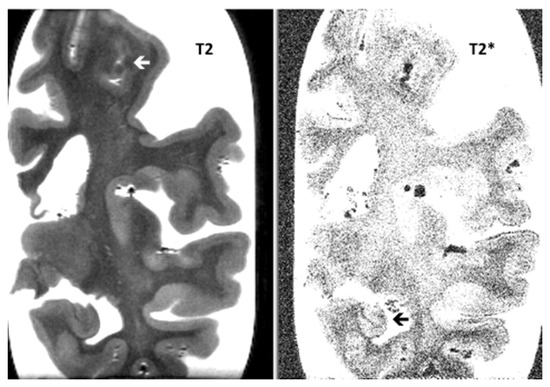

Post-Mortem 7.0-Tesla Magnetic Resonance Imaging of the Hippocampus in Progressive Supranuclear Palsy with and without Cerebral Amyloid Angiopathy

3. Results

| Hippocampal atrophy | 0.6 (0.7) | 0.9 (0.6) | NS |

| Hippocampal micro-bleeds | 0.9 (0.6) | 0.4 (0.5) | NS |